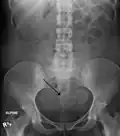

Two calcified fibroids (in the uterus)

A subserosal uterine fibroid with a diameter of 5 centimeters -